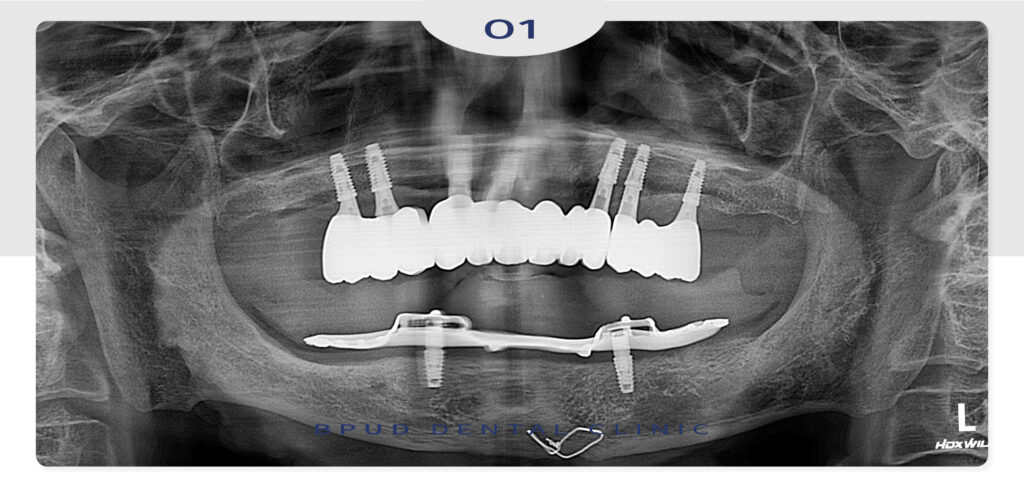

오랜 기간 틀니의 사용으로 치조골 흡수가

매우 심한 편이셨지만 안정적으로 식립과

최종 보철물까지 마친 모습입니다.

중간에 임시 틀니를 제작하여 사용에 불편함이

없도록 하고 4개월 후 보철을 마무리 하였습니다.

더 이상 불편한 틀니의 사용없이 자연치아처럼

사용할 수 있어 환자분께서도 만족도가 매우 높으셨고

하악도 임플란트를 추가 식립하여 치료를 진행할 예정입니다.